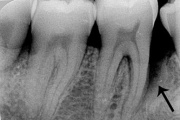

GAgP 25 aastasel suitsetaval puuduliku suuhügieeniga patsiendil